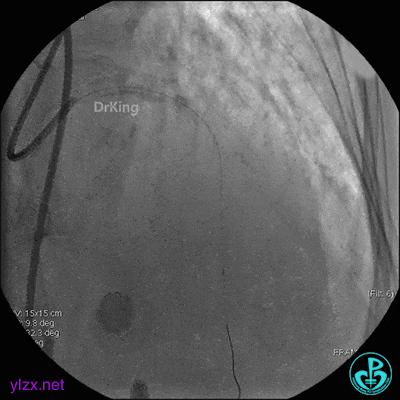

EBU指引导管到位,导丝通过闭塞段到达前降支远端,经指引导管冠脉内推注替罗非班6ml,前降支恢复3级血流,闭塞段局部残余狭窄严重,2.0×15mm球囊扩张前降支近端闭塞处后再次冠脉内推注替罗非班8ml。下台继续治疗。